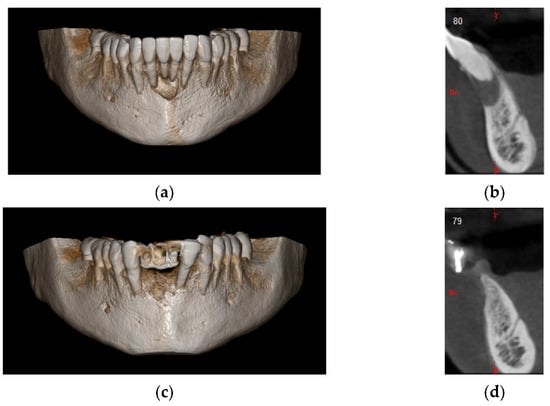

In this case, we observed how modern 3D reconstruction techniques can be a good support in regenerative surgery. In fact, starting from dicom files format, obtained with cone-beam computed tomography (CBCT) (Osteophoenix, Erandio-Vizcaya-Spain) it was possible to simulate “ex-ante” the surgical procedure. In addition to the reconstruction of the mandible (Figure 10a), the extraction of molars 4.6 and 4.7 was also simulated.

Figure 10.

(a) 3D model of the mandible; (b) Titanium foil digital design.

A titanium foil barrier was preventively designed and prepared in order to shorten surgical time (Figure 10b). In fact, the great advantage in cases like this is that the device does not need to be shaped during the surgical session.

4 months after the surgery, the barrier was withdrawn and, behind it, growth of elastic and thick osteoid tissue was observed (Figure 16a,b). After further 4 months, a CBCT was performed, and the amount of regenerated bone was observed (Figure 17a–d).

Figure 17.

(a) Initial 3D situation; (b) CBCT of the initial situation; (c) Final CBCT post 3D regeneration after 4 months; (d) X-ray of the situation post regeneration after 4 months.